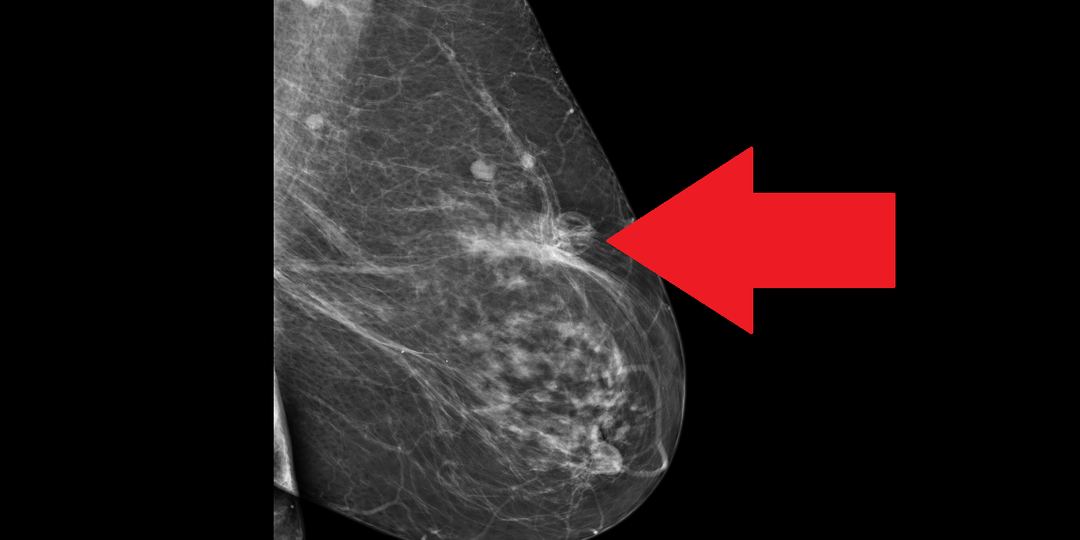

Сегодня расскажу историю пациентки, которой около 7 лет назад был установлен диагноз рак молочной железы. Биопсия подтвердила инвазивный характер опухоли, по данным иммуногистохимического (ИГХ) исследования опухоль оказалась гормонзависимой (люминальной), HER2-негативной. По данным комплексного обследования признаков отдаленного метастазирования не выявлено, установлена II стадия заболевания. Выполнена мастэктомия с реконструктивной пластикой имплантом, назначена гормонотерапия тамоксифеном. Через три года по данным контрольного обследования было диагностировано метастатическое поражение костей. Назначена терапия ингибиторами ароматазы в комбинации с рибоциклибом, а также деносумаб. Менее чем через год рибоциклиб пришлось отменить из-за выраженной гепатотоксичности (печеночные ферменты АСАТ и АЛАТ повысились до нескольких сотен единиц). Но прием ингибиторов ароматазы+деносумаб был продолжен. Еще через три года у пациентки появились жалобы на ухудшение общего состояния, одышку. По дан